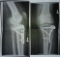

Tibiakopf-Fraktur und 'Return to sports'

Zu diesem Thema habe ich eine interessante Studie gefunden, welche unter anderem besagt, das in 9 von 11 Fällen eine Tibiakopf-Fraktur das Karriere Ende für einen Profisportler bedeutet.

Ich lese derzeit nur ab und zu hier im forum mit :? . Irgendwie schade, aber für mich gibt es einfach nicht viel Neues zum Mitreden. Möchte aber deine Fragen beantworten. Also für mich geht gottseidank jede Art von Sport wieder, die OP ist allerdings schon über 7 Jahre (Metallentfernung über 6 Jahre) her. Ich bin auch im 1. Jahr (mit Erlaubnis vom Arzt) mit den 7 Schrauben im Knie wieder Skifahren und Rennrodeln gewesen, und habe auch einige Rennen (ein bischen gebremst) bestritten. Obwohl ich mich super vorbereitet habe, war das Skifahren zwar möglich, aber nicht so wie ich es eigentlich gewohnt war (kraftvolles carven) sondern eher ein fröhliches "herunterwedeln". Aber es ging, auch mehrere Tage z.b. 5 hintereinander, ohne Schmerzen. Die Kraft fehlte allerdings und das Knie war einfach nicht so ganz stabil wie früher, auch wenn ich im Alltag gar nichts mehr spürte. Vermutlich habe ich einfach unbewusst das Knie geschont und hatte ein wenig Angst - Kopfsache. Erst nach dem 2. Jahr ging es merklich besser, ab dem 3. Jahr ohne Einschränkungen :mrgreen: .

Meine Erfahrung ist also, dass man 1-2 Jahre auch dann beeinträchtigt ist, wenn man viel trainiert, ab dem 3. Jahr geht alles wieder. Voraussetzung ist aber sicher eine perfekte OP wie dies bei mir offensichtlich der Fall war, sonst glaube ich wird Sporteln ziemlich zäh gehen :evil: .